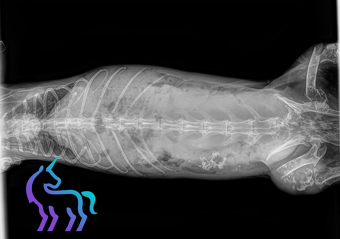

La stérilisation chez la lapine implique le retrait non seulement des ovaires, mais également de l’utérus. Cette intervention, appelée ovario-hystérectomie, est plus lourde que la simple ovariectomie pratiquée chez les chattes.